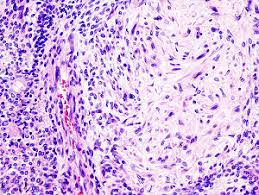

Pleomorphic adenoma is a benign salivary gland tumor that exhibits wide cytomorphologic and architectural diversity.

The tumor has the following three components:

An epithelial cell component

A myoepithelial cell component

A stromal (mesenchymal) component

Identification of these three components, which may vary quantitatively from one tumor to another, is essential to the recognition of pleomorphic adenoma.